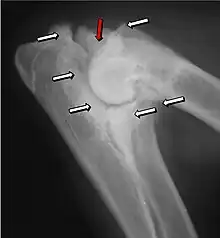

Most primary lesions are related to osteochondrosis, a disease of the joint cartilage, and osteochondritis dissecans (OCD), the separation of a flap of cartilage on the joint surface. Other common causes of elbow dysplasia include an ununited anconeal process (UAP) and fragmented or ununited medial coronoid process (FCP or FMCP).[1]

In OCD, the normal change of cartilage to bone in the development of the joint fails or is delayed. The cartilage continues to grow and may split or become necrotic. The cause is uncertain, but possibly includes genetics, trauma, and nutrition (including excessive calcium and decreased vitamin C intake).[4] OCD lesions found in the elbow at the medial epicondyle of the humerus are caused by disturbed endochondral fusion of the epiphysis of the medial epicondyle with the distal end of the humerus, which may in turn be caused by avulsion of the epiphysis.[5] Specific conditions related to OCD include fragmentation of the medial coronoid process of the ulna (FMCP) and an ununited anconeal process of the ulna (UAP). All types of OCD of the elbow are most typically found in large breed dogs, with symptoms starting between the ages of 4 and 8 months.[4] Males are affected twice as often as females. The disease often affects both elbows (30 to 70 percent of the time), and symptoms include intermittent lameness, joint swelling, and external rotation and abduction of the paw.[6] Osteoarthritis will develop later in most cases.

UAP is caused by a separation from the ulna of the ossification center of the anconeal process.[7] FMCP is caused by a failure of the coronoid process to unite with the ulna.